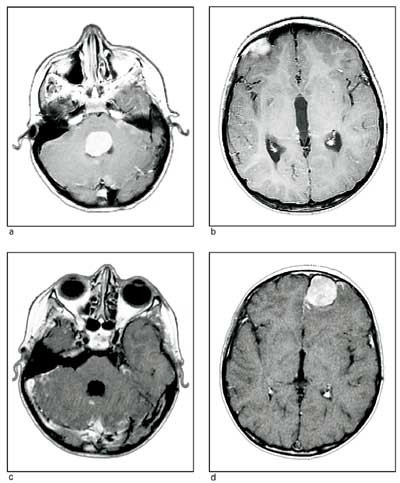

Disse utgår fra astrocytter. Etter WHO-klassifiseringen deles de inn i malignitetsgrad 1 – 4 (6). Grad 3 og 4, de maligne, er sjeldne hos barn. Astrocytom grad 1 (pilocytisk astrocytom) og grad 2 (fibrillært astrocytom), kalt lavgradige astrocytomer, er hyppigere hos barn enn hos voksne. Den vanligste varianten er pilocytisk astrocytom i cerebellum (fig 1), en godartet svulst dersom man oppnår radikal fjerning.

Medulloblastomer er udifferensierte nevroepiteliale svulster(primitiv nevroektodermal tumor, PNET) i lillehjernen, oftest nær midtlinjen (fig 2). De er høymaligne og har uttalt tendens til spredning i subaraknoidalrommet via cerebrospinalvæsken. Tilsvarende svulster i storhjernen kalles nevroblastomer, i corpus pineale pineoblastomer.

Fra bakre skallegrop vil symptomene svært ofte skyldes en påvirkning eller skade av lokale strukturer (lillehjerne, hjernenerver eller hjernestamme) i kombinasjon med et generelt økt intrakranialt trykk, som kommer som en følge av avklemming av hjernevæskedrenasjen og hydrocephalusutvikling (fig 1). Hos barn i første leveår kan økende hodeomkrets lenge være eneste symptom. Hos eldre barn er kardinalsymptomet hodepine. Denne kommer ofte gradvis, og med mest uttalte plager om morgenen. Smertene kan være lokalisert til nakke/bakhode eller mer diffust. Det vil ofte være kvalme og morgenbrekninger, i avanserte stadier bevissthetsforstyrrelser, og til slutt ev. herniering og død. Papillødem er ofte til stede når diagnosen stilles.

Lavgradige cerebellare astrocytomer behandles kirurgisk. Total ekstirpasjon av svulsten (verifisert med umiddelbar postoperativ MR) er som regel kurativt (9, 19, 20) (fig 1). Hvis det er resttumor, bør ny operasjon overveies. Dersom svulsten residiverer etter antatt radikal operasjon, skal pasienten opereres på nytt. Kjemoterapi eller strålebehandling er kun unntaksvis indisert. Lavgradige astrocytomer sprer seg ikke via hjernevæsken, og alle residiver er lokale. I perioden 1960 – 2001 ble 110 pasienter i aldersgruppen 0 – 19 år behandlet for lavgradig cerebellart astrocytom ved Nevrokirurgisk avdeling, Rikshospitalet (9). Femårs, tiårs og 20-års overlevelse var henholdsvis 90 %, 87 % og 85 %. Total ekstirpasjon var en sikker gunstig prognostisk faktor. De fleste langtidsoverlevere hadde et godt funksjonelt resultat ved oppfølgingsundersøkelsen, bare 10 % et dårlig.

Medulloblastomer

Disse sprer seg via hjernevæsken til hele det kraniospinale rom (fig 2). Behandlingen må derfor rettes mot hele nevroaksen og består derfor i å fjerne så mye som mulig av svulsten, deretter gis kjemoterapi og kraniospinal strålebehandling hvis barnet er over tre år (10, 13, 17, 21). Femårs og tiårs overlevelse med dette behandlingsregimet er i Norge henholdsvis 53 % og 45 % (7). Tilsvarende er rapportert fra andre sentre (10, 22). Ingen kan kureres med kirurgi alene (7, 23). Barn under tre år får et intensivt kjemoterapiregime etter operasjonen.